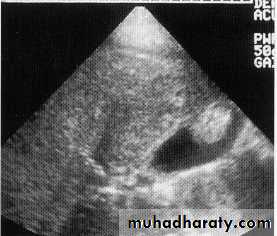

Hepatic , renal cyst